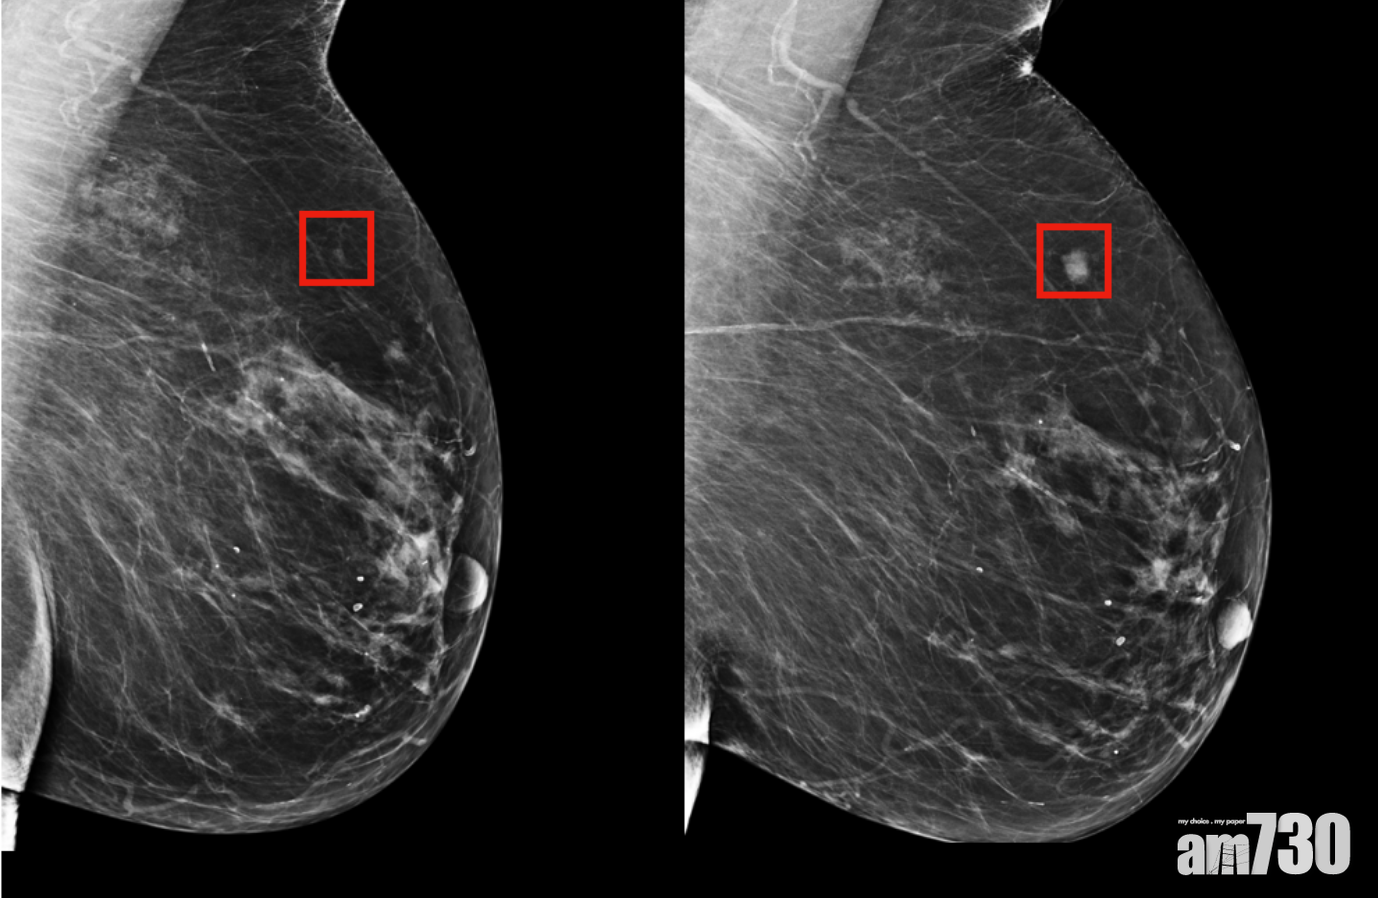

系統通過學習多達90,000張乳房X光片,能夠辨識出乳房組織的任何一個微妙複雜變化。(MIT)

由美國麻省理工學院的「MIT計算機科學與人工智能實驗室」,聯同馬薩諸塞州綜合醫院的團隊,創建了一種新深度學習AI模型,比起傳統醫生從檢查人士的X光片識別出有可能患乳癌的費時做法,系統通過學習多達90,000張乳房X光片,能夠細緻地辨識出乳房組織的任何一個微妙複雜變化,藉此演算出未來5年患乳癌的機率。團隊稱新系統檢測出最高風險的可靠有31%,相比其他模型的18%還要高。